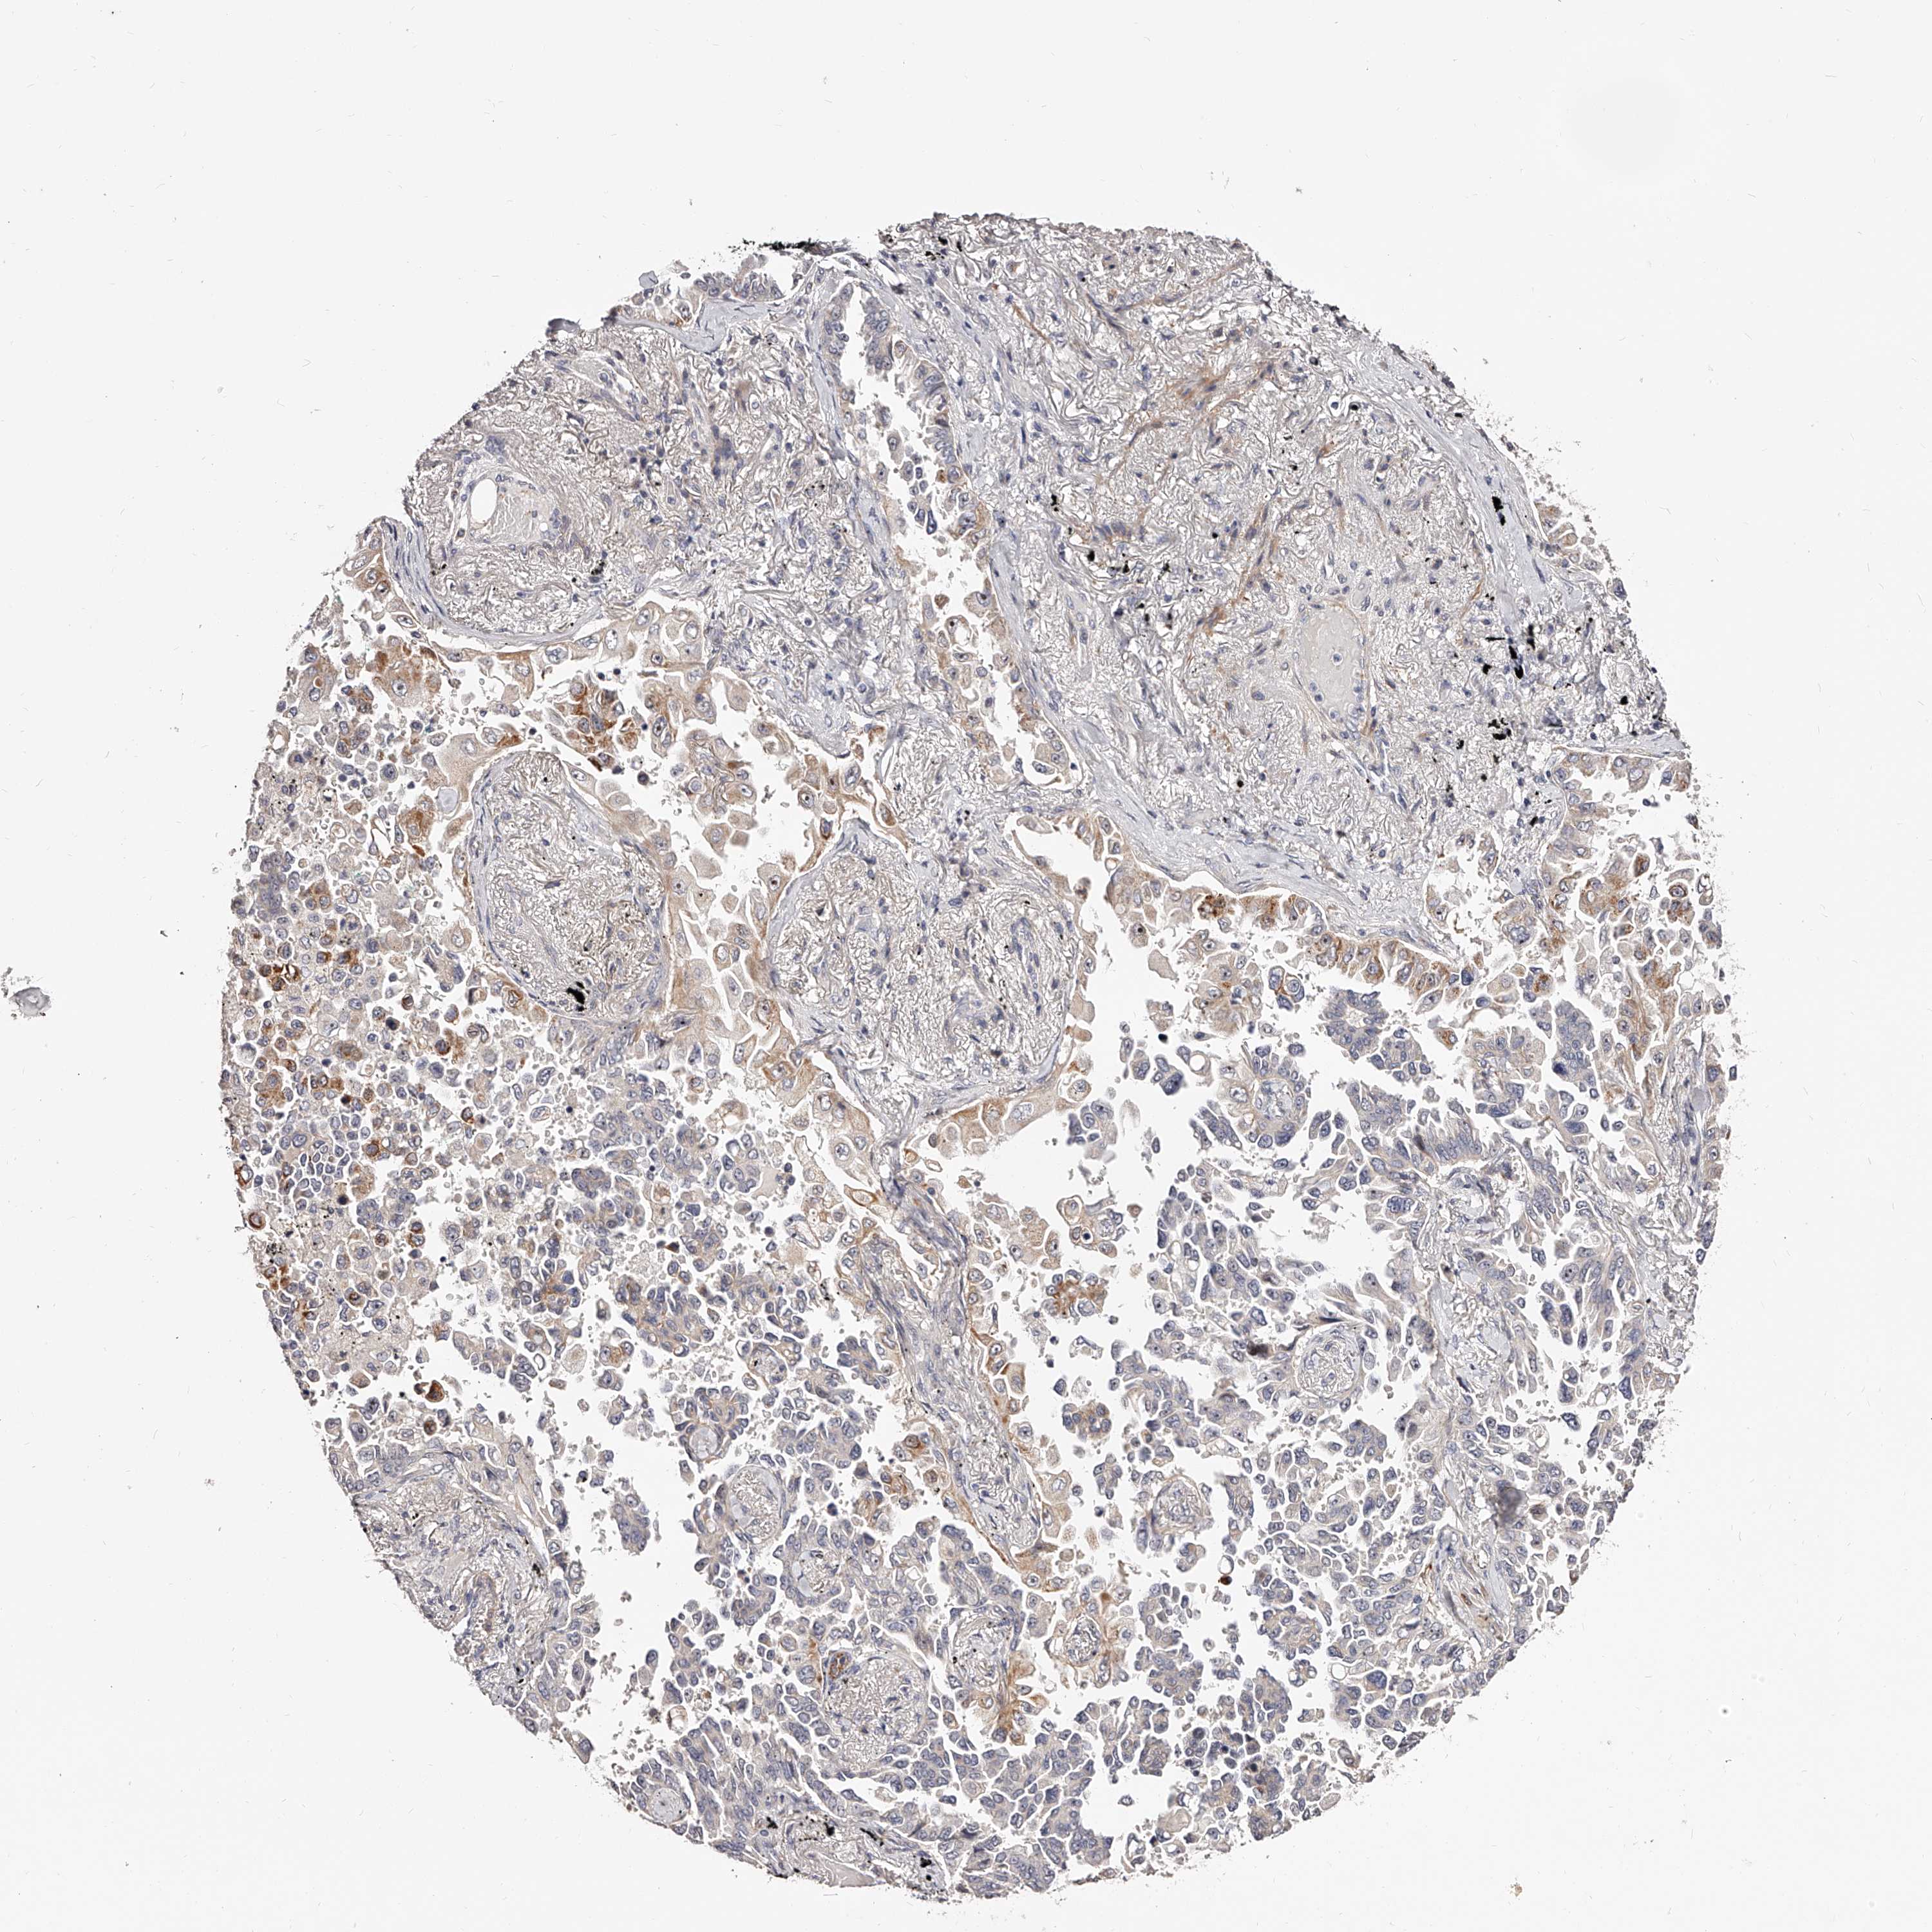

LUNG SQUAMOUS CELL CARCINOMA (TCGA) - Interactive survival scatter ploti

The Survival Scatter plot shows the clinical status (i.e. dead or alive) for all individuals in the patient cohort, based on the same data that underlies the corresponding Kaplan-Meier plots. Patients that are alive at last time for follow-up are shown in blue and patients who have died during the study are shown in red.

The x-axis shows the expression levels (FPKM) of the investigated gene in the tumor tissue at the time of diagnosis. The y-axis shows the follow-up time after diagnosis (years). Both axes are complimented with kernel density curves demonstrating the data density over the axes. The top density plot shows the expression levels (FPKM) distribution among dead (red) and alive patients (blue). The right density plot shows the data density of the survived years of dead patients with high and low expression levels respectively, stratified using the cutoff indicated by the vertical dashed line through the Survival Scatter plot. This cutoff is automatically defined based on the FPKM cutoff that minimizes the p-score. The cutoff can be changed by dragging the vertical line or by entering a cutoff value in the square labeled "Current cut-off".

Under the Survival Scatter plot the p-score landscape (black curve; left axis) is shown together with dead median separation (red curve; right axis). Dead median separation is the difference in median mRNA expression between patients who have died with high and low expression, respectively. It is calculated as follows: median FPKM expression of dead patients with high expression - median FPKM expression of dead patients with low expression. This is intended to aid the user in visually exploring custom cutoffs and the associated p-scores and dead median separation.

Individual patient data is displayed and can be filtered by clicking on one or more of the category buttons on the top of the page. Categories describing expression level and patient information include: high, low, alive, dead, female, male and tumor stages. The scale of the x-axis can be toggled between linear and log-scale by clicking on the "x log" button. Mouse-over function shows TCGA ID, patient information and mRNA expression (FPKM) for each patient.

& Survival analysisi

Kaplan-Meier plots summarize results from analysis of correlation between mRNA expression level and patient survival. Patients were divided based on level of expression into one of the two groups "low" (under cut off) or "high" (over cut off). X-axis shows time for survival (years) and y-axis shows the probability of survival, where 1.0 corresponds to 100 percent.

ZNF502 is not prognostic in Lung Squamous Cell Carcinoma (TCGA)

Best expression cut offi

Based on the FPKM value of each gene, patients were classified into two groups and association between prognosis (survival) and gene expression (FPKM) was examined. The best expression cut-off refers the FPKM value that yields maximal difference with regard to survival between the two groups at the lowest log-rank P-value. Best expression cut-off was selected based on survival analysis .

When clicking on this number, the vertical dashed line indicating cut-off, the interactive survival plot, and the Kaplan-Meier curve will be adjusted to show results based on the best expression cut-off.

: 1.48

P scorei

Log-rank P value for Kaplan-Meier plot showing results from analysis of correlation between mRNA expression level and patient survival.

N/A

TCGA RNA samplesi

RNA-seq data is reported as average FPKM (number Fragments Per Kilobase of exon per Million reads), generated by the The Cancer Genome Atlas (TCGA) .

Normal distribution across the dataset is visualized with box plots, shown as median and 25th and 75th percentiles. Points are displayed as outliers if they are above or below 1.5 times the interquartile range. FPKM values of the individual samples are presented next to the box plot.

Average pTPM 1.0

Number of samples 489